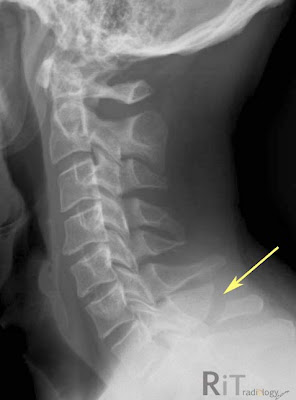

A lateral cervical spine radiograph and sagittal-reformatted CT image show an oblique fracture of the C7 vertebra with slight displacement. There is no extension to the lamina or facet joint on axial CT (not shown).Clay Shoveler Fracture

- Avulsion, hyperflexion injury of the spinous process of C6, C7 or T1

- Typically oblique in orientation

- Due to abrupt flexion of the head and neck against tensed posterior neck ligaments

- Mechanically and neurologically stable unless it extends into the lamina. Also should look for facet joint injury or dislocation